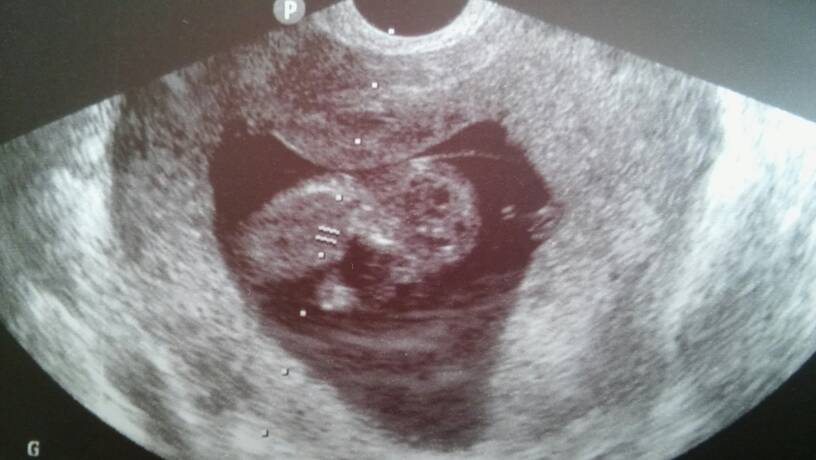

Zdjęcia z dzisiejszej wizyty.

20170316_141610.jpg

20170316_141600.jpg